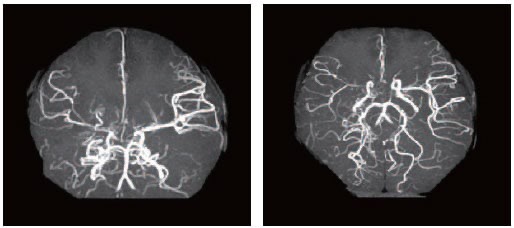

수술치료(뇌혈류 재건술, Revascularization surgery)

모야모야병의 핵심 치료는 뇌혈류 공급을 위한 새로운 통로를 만들어주는 수술입니다.

① 직접 우회술(Direct bypass)

• 측두동맥(STA)을 직접 뇌혈관(MCA)과 연결해 혈류를 즉시 공급하는 방식 • 성인에서 가장 많이 시행

• 수술 직후부터 혈류 개선 효과가 빠르게 나타납니다.

② 간접 우회술(Indirect bypass)

• 근육이나 막 조직을 뇌 표면에 붙여 그 조직에서 자라는 새로운 혈관이 뇌를 공급하도록 유도 • 소아에서 많이 사용

• 혈류 증가 효과가 나타나기까지 수개월이 필요합니다.

③ 혼합 우회술(Combined bypass)

• 직접 + 간접 방법을 동시에 시행하는 방식

• 빠른 효과 + 장기 안정성을 동시에 노릴 수 있는 방법입니다.